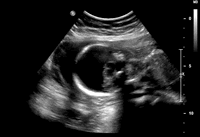

胎儿染色体异常的超声诊断

胎儿常见染色体异常包括21三体(47,XX+21;47,XY+21)、18三体(47,XX+18;47,XY+18)、13三体(47,XX+13;47,XY+13)、Turner 综合征(45,X0)和三倍体(69,XXY)等。

常见染色体异常的特征性超声表现

21三体 常见特征性超声表现是十二指肠闭锁引起的双泡征和鼻骨异常。考虑十二指肠闭锁时注意:①要与其他囊性包块鉴别,如胆囊和胆总管囊肿、肾囊肿、肝囊肿等;②要注意寻找双泡之间的幽门管;③要注意胃蠕动,排除一过性双泡征。孕早期检查时要注意是否存在鼻骨缺失,根据该特征对21三体的诊断率为73%,假阳性率0.5% ......